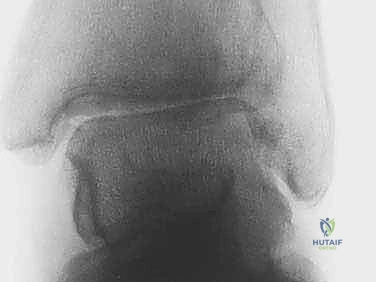

عملية دمج أو تثبيت الكاحل (Arthrodesis) تهدف إلى إزالة الأسطح الغضروفية التالفة بالكامل، ثم وضع عظمة الظنبوب وعظمة الكعب في وضعية تشريحية صحيحة، وتثبيتهما معاً باستخدام براغي أو صفائح معدنية. بمرور الوقت (عادة 8 إلى 12 أسبوعاً)، ينمو عظم جديد بين العظمتين، ليلتحما وتصبحا عظمة واحدة صلبة. بمجرد توقف الحركة في هذا المفصل التالف، يتوقف الألم تماماً.

تاريخياً، كانت هذه العملية تُجرى عبر شق جراحي كبير (الجراحة المفتوحة). ولكن مع التطور التكنولوجي، أصبح الأستاذ الدكتور محمد هطيف يعتمد على تقنية المنظار الجراحي (Arthroscopy) كخيار أول للحالات المناسبة.